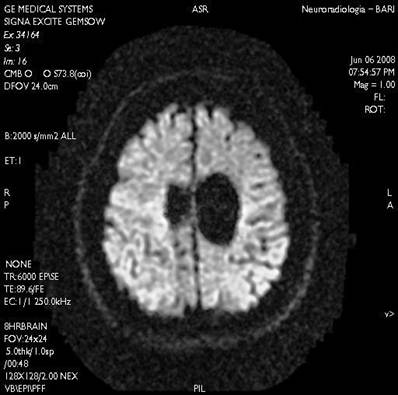

In order to achieve diagnostic certainty, we performed Computed Tomography (CT) in the emergency setting, Nuclear magnetic resonance (NMR) of the brain and Magnetic Resonance Angiography of intracranial vessels. (Figs. 3,4,5)

Fig 5

Magnetic Resonance Angiography of intracranial vessels

Int J Med Sci Image Int J Med Sci Image

The Magnetic Resonance Angiography did not reveal malformations or intracranial vascular anomalies.